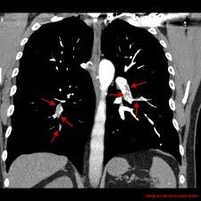

Niestabilność hemodynamiczna u chorych poddawanych embolektomii tętnicy płucnej: doświadczenia własne

Zator tętnicy płucnej jest główną przyczyną chorobowości I śmiertelności wśród chorych poddawanych zabiegom kardiochirurgicznym w trybie pilnym, z całkowitą śmiertelnością wahającą się od 6% do aż 85%. Choć leczeniem pierwszego rzutu jest postępowanie niechirurgiczne lub interwencja przezskórna, to u chorych we wstrząsie kardiogennym leczenie operacyjne ciągle pozostaje metodą z wyboru. Nasz ośrodek regularnie wykonuje operacje embolektomii tętnicy płucnej, których rezultat jest lepszy, niż podają aktualne doniesienia. W związku z tym przeprowadziliśmy retrospektywną analizę wyników leczenia chorych z zatorem tętnicy płucnej i rodzaju anestetyków stosowanych podczas leczenia.